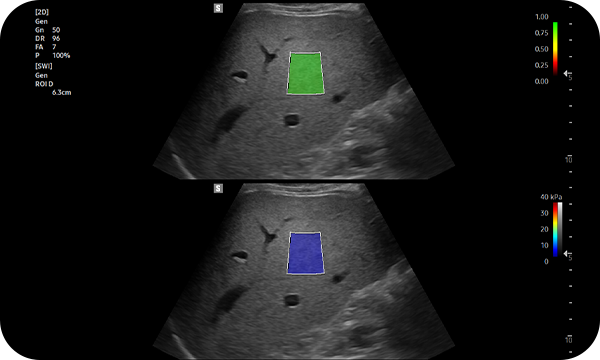

S-Shearwave Imaging™ allows for non-invasive assessment of the stiffness of tissue/lesions liver. The color-coded elastogram, quantitative measurements, dual or single display option, and user-selectable ROI functions are especially useful for the accurate diagnosis liver diseases.